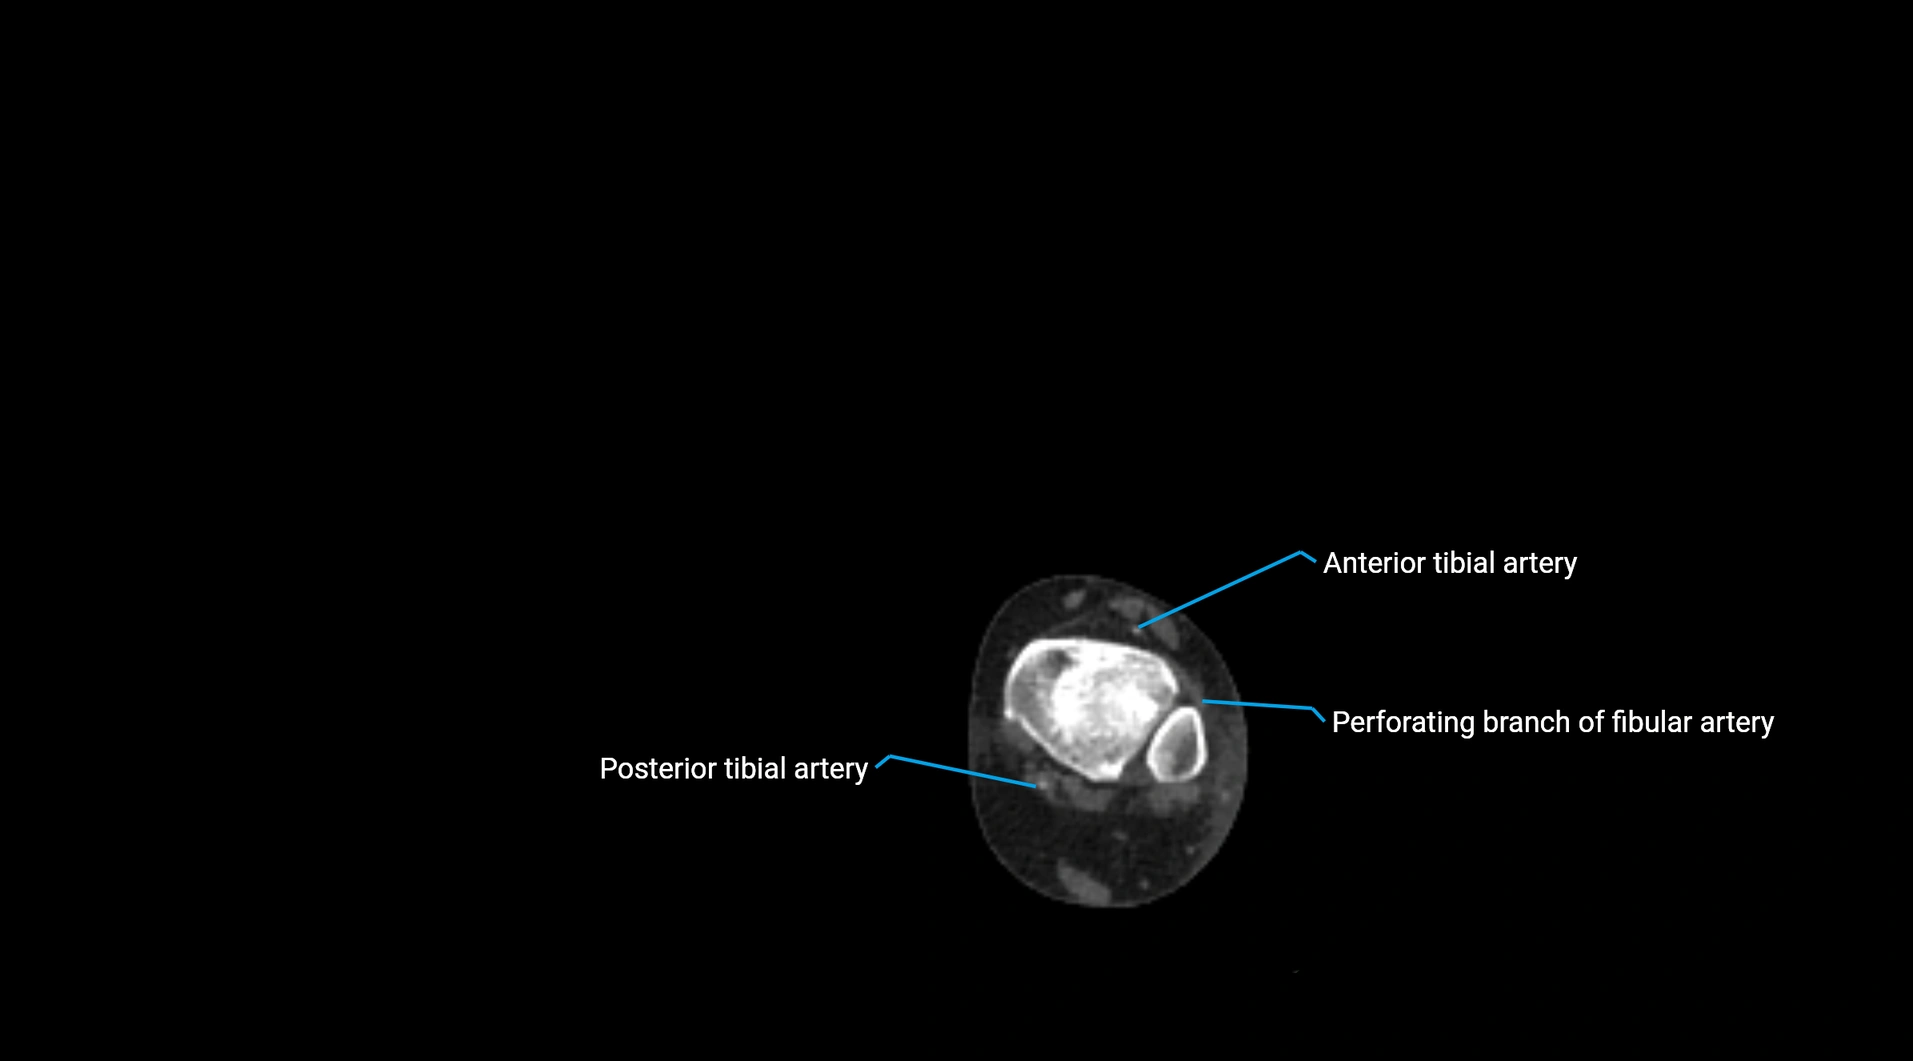

CT Appearance

Non-contrast CT:

• Appears as a tubular soft tissue structure anterior to vertebral bodies

• Calcified atherosclerotic plaques appear as hyperdense foci along the wall

• Useful for screening abdominal aortic aneurysm (AAA) size and mural calcification

Contrast-enhanced CT (CTA):

• Gold standard for abdominal aortic imaging

• Provides excellent detail of lumen, wall, aneurysm, thrombus, and branch vessels

• Multiplanar and 3D reconstructions help in aneurysm measurement, stent graft planning, and dissection evaluation

• Detects acute rupture, traumatic injury, or occlusion with high sensitivity